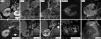

Se presenta como un tumor periférico circunscrito (pequeño y homogéneamente sólido o mayor quístico-hemorrágico) o como una lesión infiltrante e invasora de venas, con peor pronóstico.

Por su baja densidad vascular, el realce es menor que en otras neoplasias renales, lo que facilita su caracterización. En tomografía computarizada puede no realzar de manera concluyente, y entonces es indistinguible de un quiste hiperatenuante. La ecografía con contraste y la resonancia magnética son más sensibles para detectar vascularización. Son además característicos un patrón vascular específico, hipointensidad en T2, restricción de la difusión del agua y aumento de señal en fase opuesta.

It presents as a circumscribed peripheral tumor (small and homogeneously solid or larger and cystic/hemorrhagic) or as an infiltrating lesion that invades the veins, which has a worse prognosis.

Due to their low vascular density, papillary renal cell carcinomas enhance less than other renal tumors, and this facilitates their characterization. On computed tomography, they might not enhance conclusively, and in these cases they are impossible to distinguish from hyperattenuating cysts. Contrast-enhanced ultrasonography and magnetic resonance imaging are more sensitive for detecting vascularization. Other characteristics include a specific vascular pattern, hypointensity on T2-weighted images, restricted water diffusion, and increased signal intensity in opposed phase images.